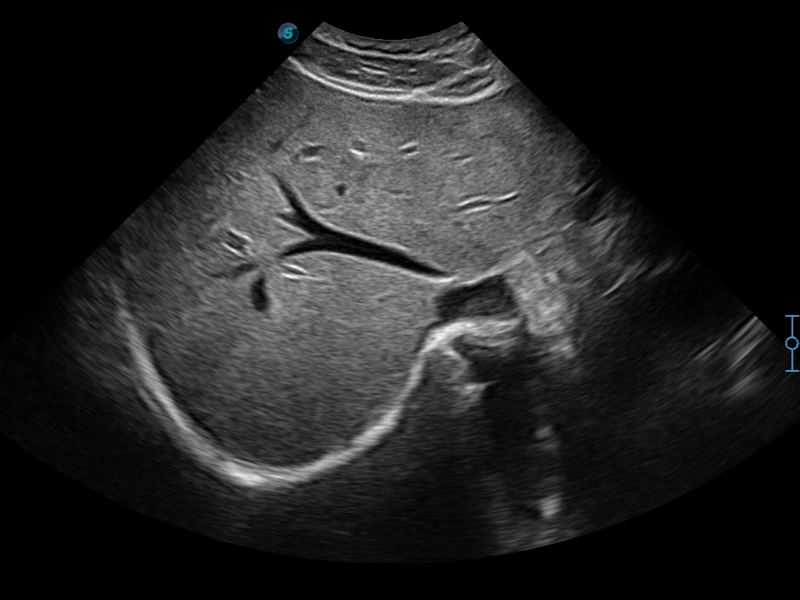

開立醫(yī)療通過不斷的技術(shù)創(chuàng)新,為大眾的生命健康提供持續(xù)關(guān)愛。P12 Plus采用全新一代超聲成像平臺,新平臺旨在將真實還原組織解剖結(jié)構(gòu)作為首要目標(biāo)。平臺采用全新集成化硬件模塊,搭載新一代芯片,系統(tǒng)性能得到大幅提升,為您的診斷提供了豐富的臨床信息。優(yōu)異的圖像表現(xiàn),豐富的探頭配置,全面的應(yīng)用功能,為您日常診斷提供了可靠的助手。

P12 Plus

彩色多普勒超聲診斷系統(tǒng)